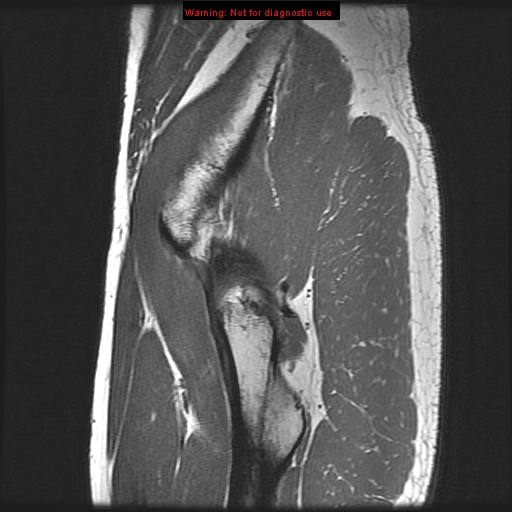

psoas muscle gluteus minimus muscle

obturator internus muscle acetabular labrum